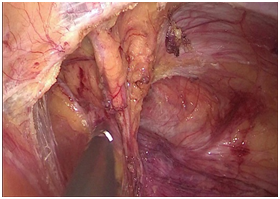

腹腔镜术中照片

手术图片

腹腔镜直肠癌根治术

腹腔镜胃癌根治术

腹腔镜结肠癌根治术。